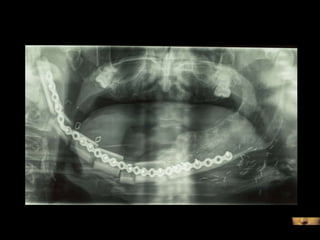

Moldeado previo de la placa

Mejor planificación estética Y funcional mandibular en el auto trasplante de tejidos. Disminución del tiempo quirúrgico en el modelado de la placa mandibular 60´. Mantenimiento de la relación céntrica. Mayor exactitud con la “técnica en espejo”.

Evitar contaminación de campos. Mayor eficiencia al planificar y realizar las osteotomías mandibulares. Mayor eficiencia al planificar y realizar las osteotomías del peroné.

Mejor planificación estéticaY funcional mandibular en el auto trasplante de tejidos. Disminución del tiempo quirúrgico en el modelado de la placa mandibular 60´. Mantenimiento de la relación céntrica. Mayor exactitud con la “técnica en espejo”.

Evitar contaminación decampos. Mayor eficiencia al planificar y realizar las osteotomías mandibulares. Mayor eficiencia al planificar y realizar las osteotomías del peroné.